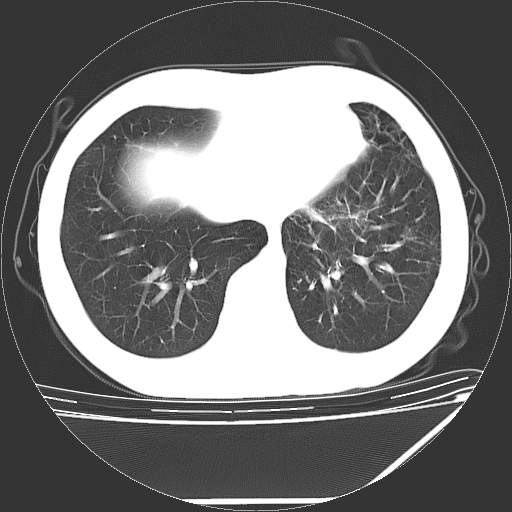

男,13岁,咳嗽、咳痰伴发热一周。

中上纵隔见多枚淋巴结肿大,部分相互融合成团片,左肺门增大,上叶支气管变窄,肺内多处斑片状 索条状及棉絮状致密影。临床“男,13岁,咳嗽、咳痰伴发热一周。”首先考虑:原发综合征!不除外淋巴瘤可能!

中上纵隔见多枚淋巴结肿大,部分相互融合成团片,左肺门增大,上叶支气管变窄,左肺支气管血管束增粗,可见磨玻璃样影。临床“男,13岁,咳嗽、咳痰伴发热一周。”首先考虑:淋巴瘤可能性大!

左肺野见淡片状影,病因整体多考虑结核

单纯看片子感觉左侧肺通气不畅,而不像肺内病变引起的纵隔病变。而且纵隔及左肺门都有淋巴结增大。首先还是考虑一下结节病,不排除淋巴瘤!!!